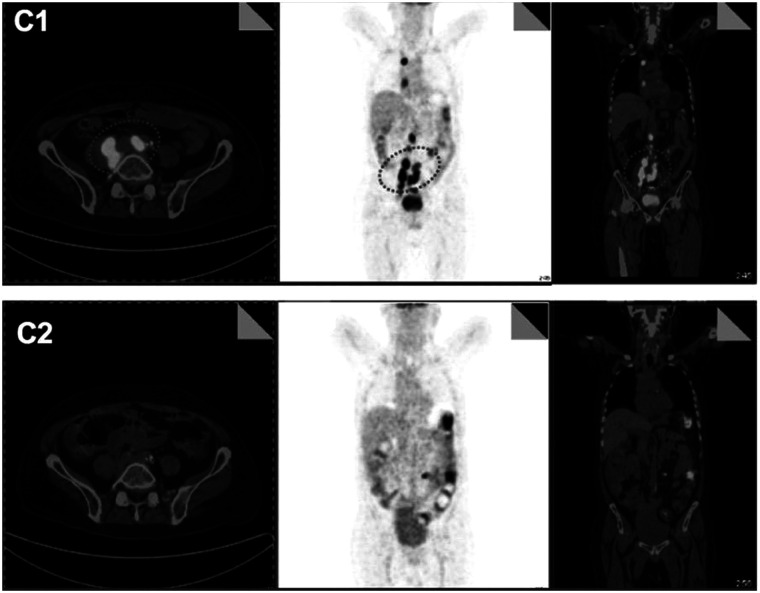

Chimeric antigen receptor (CAR)-T cell-based immunotherapy has emerged as a path-breaking strategy for certain hematological malignancies. Assessment of the response to CAR-T therapy using quantitative imaging techniques such as positron emission tomography/computed tomography (PET/CT) has been broadly investigated. However, the definitive role of PET/CT in CAR-T therapy remains to be established. [18F]FDG PET/CT has demonstrated high sensitivity and specificity for differentiating patients with a partial and complete response after CAR-T therapy in lymphoma. The early therapeutic response and immune-related adverse effects such as cytokine release syndrome and immune effector cell-associated neurotoxicity syndrome can also be detected on [18F]FDG PET images. In otherwise asymptomatic lymphoma patients with partial response following CAR-T therapy, the only positive findings could be abnormal PET/CT results. In multiple myeloma, a negative [18F]FDG PET/CT after receiving B-cell maturation antigen-directed CAR-T therapy has been associated with a favorable prognosis. In leukemia, [18F]FDG PET/CT can detect extramedullary metastases and treatment responses after therapy. Hence, PET/CT is a valuable imaging tool for patients undergoing CAR-T therapy for pretreatment evaluation, monitoring treatment response, assessing safety, and guiding therapeutic strategies. Developing guidelines with standardized cutoff values for various PET parameters and tumor cell-specific tracers may improve the efficacy and safety of CAR-T therapy.